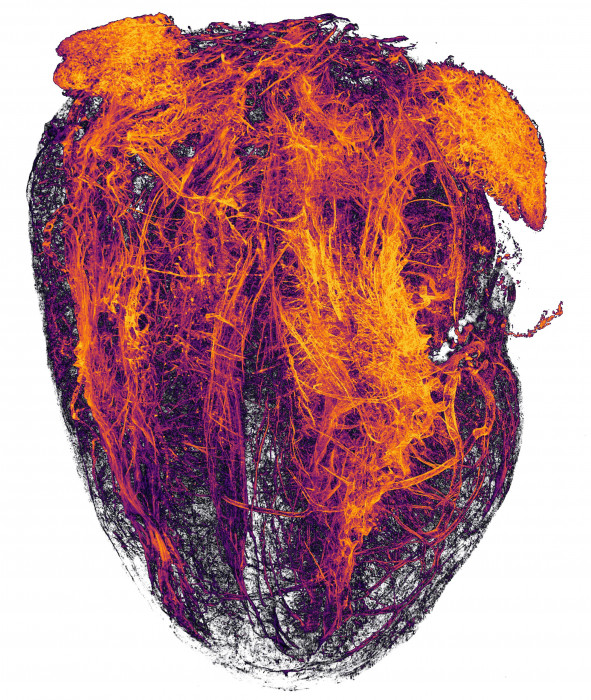

Είκοσι μοναδικές εικόνες βραβεύτηκαν στον διαγωνισμό μικροφωτογραφίας της Nikon. Πρόκειται για τον Διεθνή Διαγωνισμό Small World (Μικρόκοσμος) της Nikon. Ξεκίνησε για πρώτη φορά το 1975 ως μέσο αναγνώρισης και επικρότησης των προσπαθειών των ανθρώπων που ασχολούνται με τη φωτογραφία μέσω μικροσκοπίου. Ο συγκεκριμένος διαγωνισμός από τότε έχει γίνει ένας εξαιρετικός τρόπος προβολής μικροφωτογραφιών από μια ευρεία γκάμα επιστημονικών κλάδων.

Μια καλή φωτομικρογραφία είναι μια εικόνα της οποίας η δομή, το χρώμα, η σύνθεση και το περιεχόμενο είναι αντικείμενο ομορφιάς. Ανοιχτό σε διάφορα επίπεδα κατανόησης και εκτίμησης.

Ο Διαγωνισμός Small World της Nikon είναι ανοιχτός σε όσους ενδιαφέρονται για τη φωτογραφία μέσω μικροσκοπίου. Μεταξύ των νικητών υπάρχουν τόσο επαγγελματίες όσο και χομπίστες. Οι συμμετοχές κρίνονται από ανεξάρτητη ομάδα εμπειρογνωμόνων βάσει της πρωτοτυπίας. Αλλά και της πληροφορίας που μεταδίδει η κάθε μία, της τεχνικής επάρκειας αλλά και της εικόνας.

Δείτε παρακάτω τις 20 καλύτερες εικόνες του διαγωνισμού: